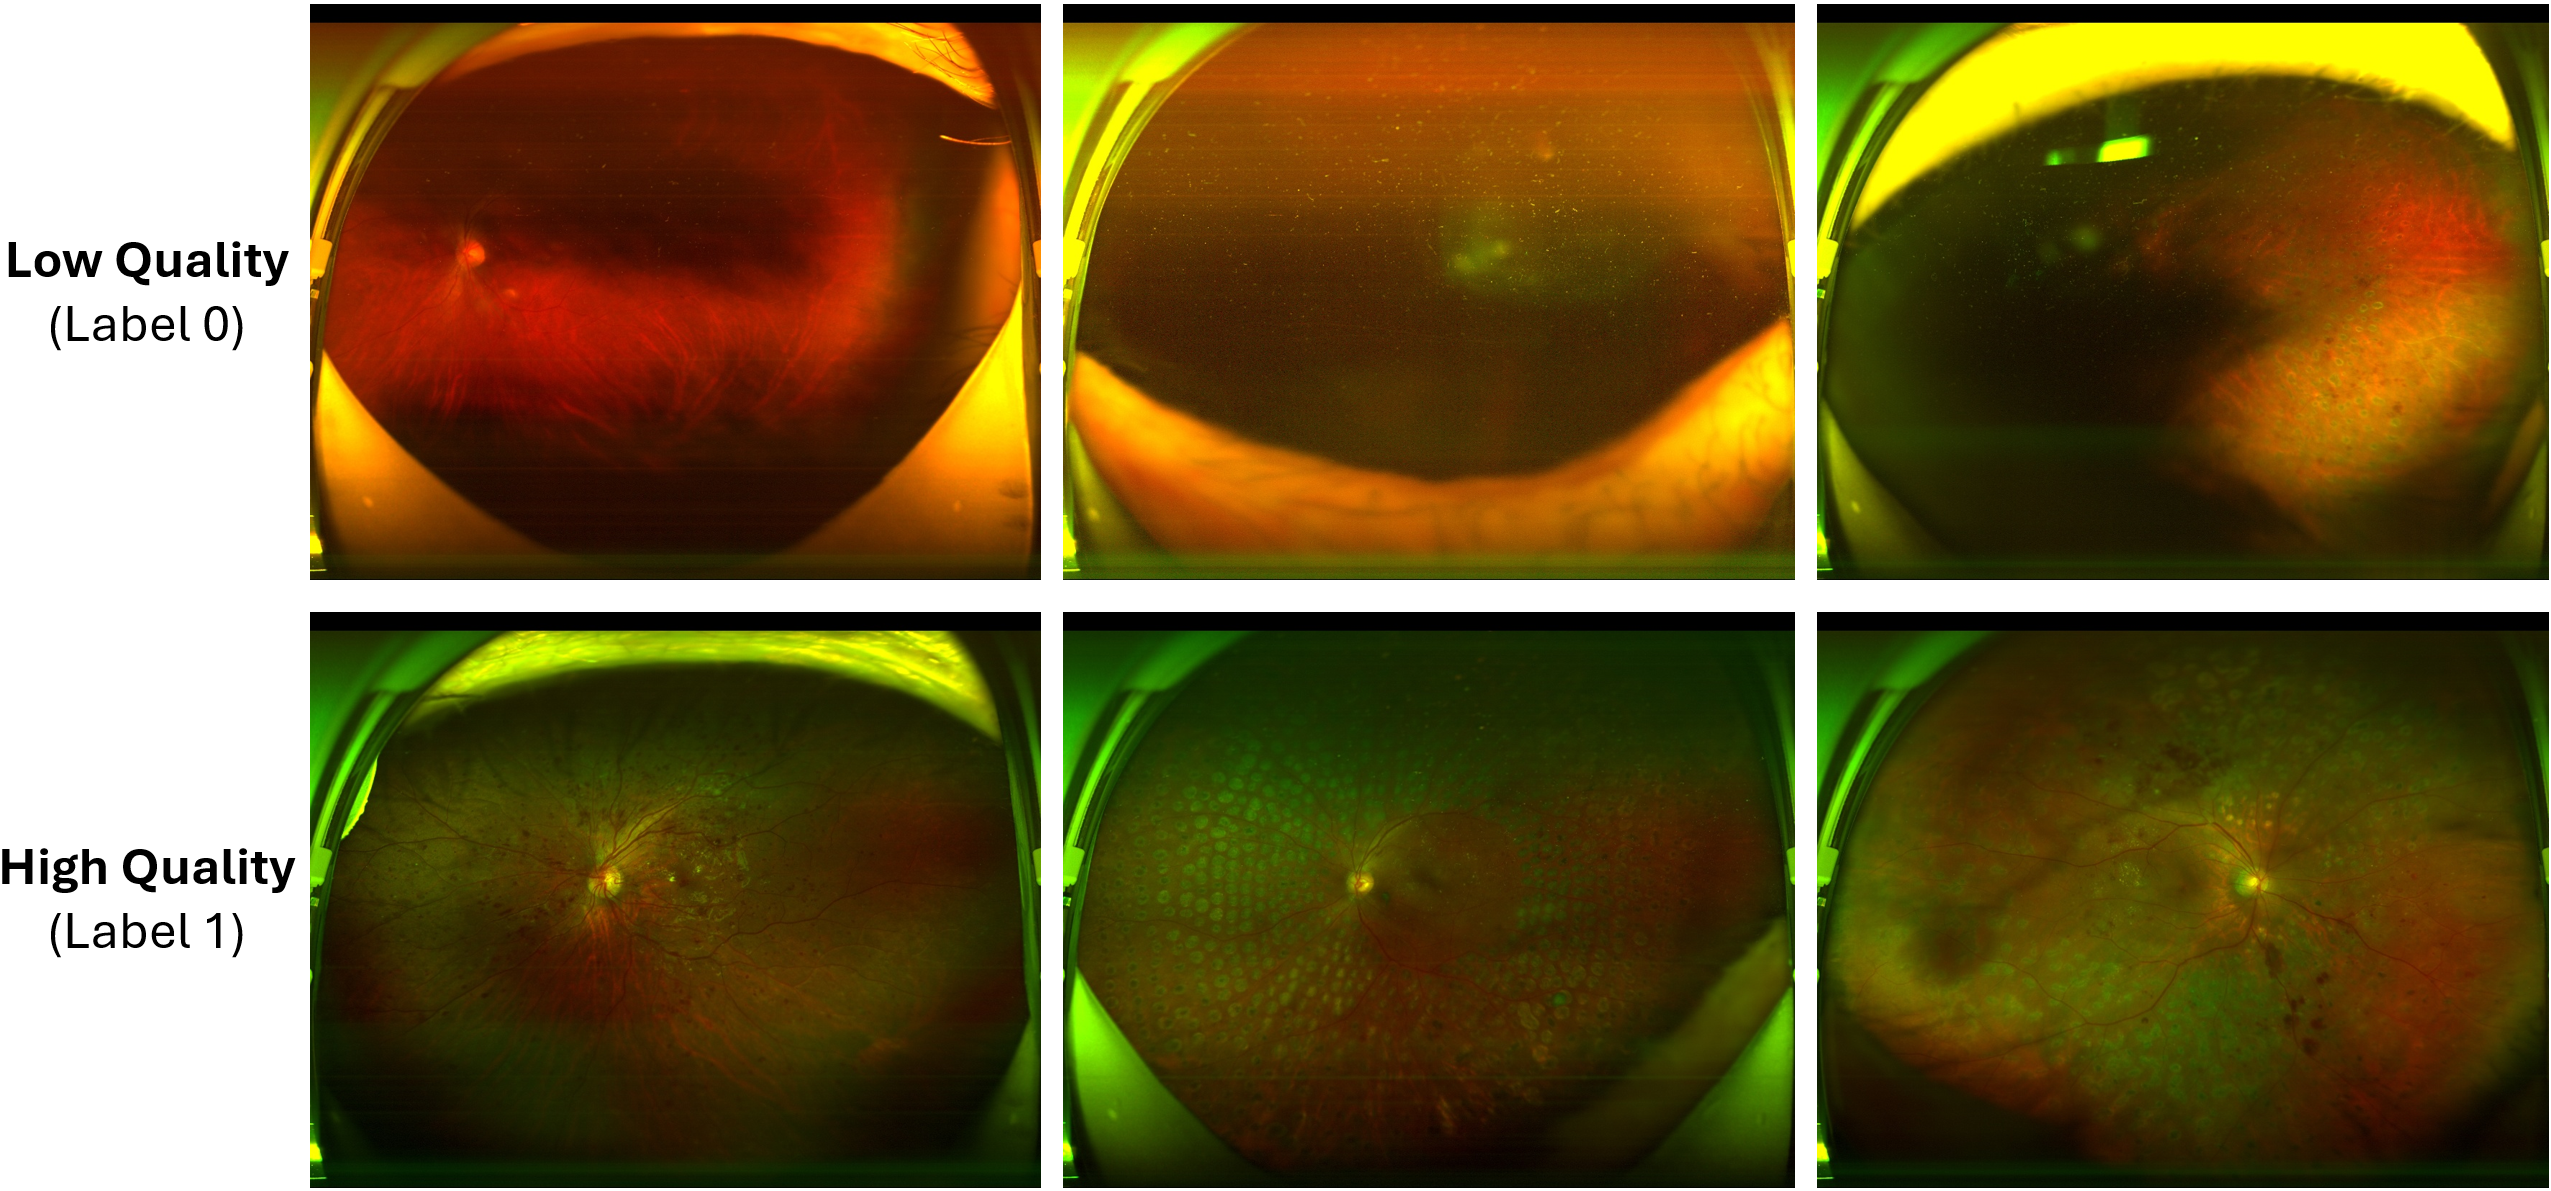

Refer to caption

Figure 3: Sample images of UWF4DR dataset, where label 0 represents the ungradable images and label 1 represents gradable images.

The images used in this study comes from the ultra-widefield (UWF) fundus imaging for diabetic retinopathy (DR) dataset, which aims to advance automatic DR analysis from UWF fundus images. The dataset includes UWF images with up to a 200-degree view of the retina, allowing the identification of predominantly peripheral lesions (PPL) that are present in a significant portion of eyes with DR. The images are classified into different DR stages based on the International Clinical Diabetic Retinopathy (ICDR) Severity Scale, ranging from no apparent retinopathy to proliferative diabetic retinopathy (PDR), including diabetic macular edema (DME). The dataset is divided into three tasks: image quality assessment, DR classification, and DME classification.

This study specifically focuses on image quality assessment for ultra-widefield fundus images. The dataset of this task contains a total of 434434 samples that include 205205 ungradable samples and 229229 gradable samples, their differences are illustrated in Figure 3. This comprehensive dataset provides a foundation for developing algorithms that assist in the timely diagnosis and management of DR patients, particularly by reducing the manual effort required for grading UWF fundus images.